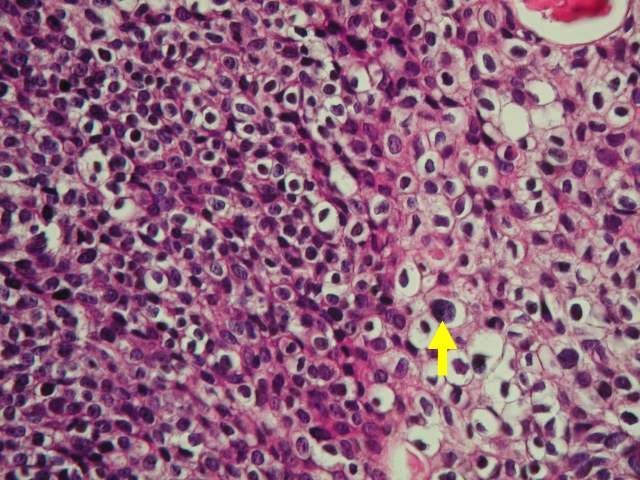

(Figure 3) Transitional cell carcinoma with tumor cells with mild to moderate nuclear

pleomorphism.